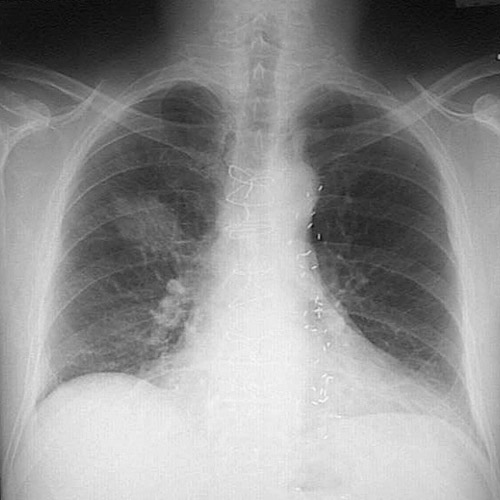

Image 6.1 The chest radiograph is shown here, with the right upper lobe mass lesion. This patient has had a previous coronary bypass graft placed, and there are vascular clips and sternal wire sutures.